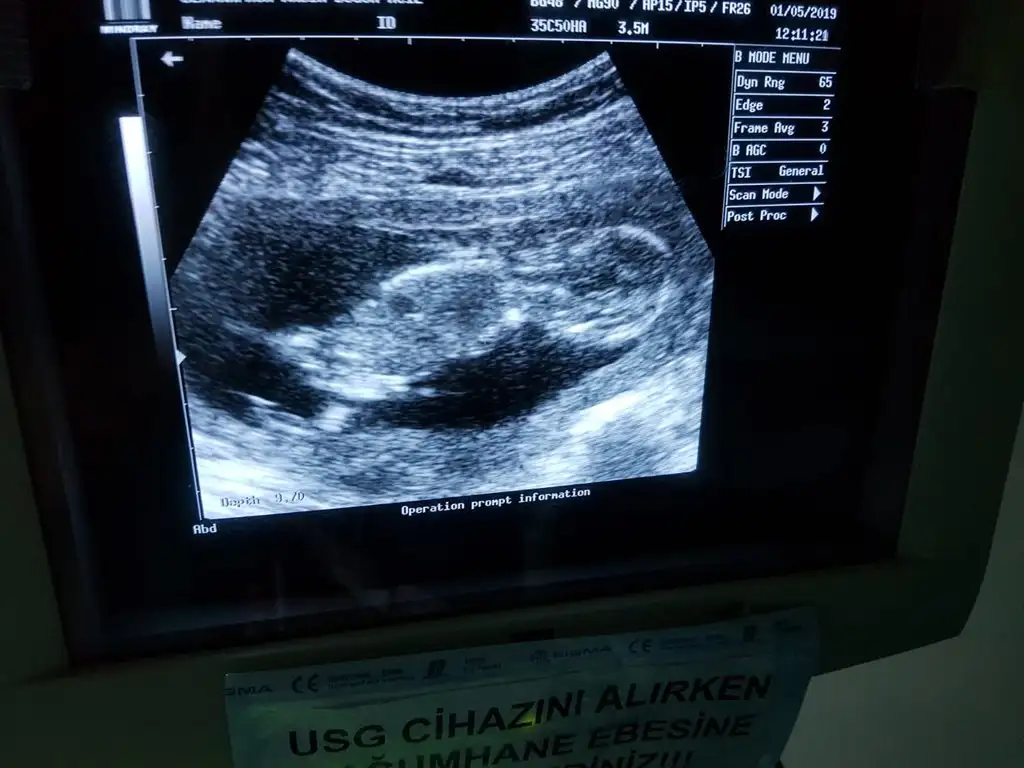

Kontrolden çıktık sata gore 12+4 ultrasona gore geriden gelen bebişim bugun 13+2 cikti :) boyu 6.5 cm olmuş ense ve burun kemiğine iyi dedi kac diye sorunca 1den kucuk merak etme sorun yok dedi doktorumkan verdim 1 hafta sonra çıkacakmış sonuç doktorum cinsiyetle ilgili de kıza benziyor ama kesin değil dedi ve ben basından beri kiz hissediyorum:) en son gittiğimde mercimek tanesi kadardı ama bugun gercekten bir bebek gordum zıplayan kayan ellerini oynatan, Rabbimin gerçekten bir mucizesi Allahım hepimize boyle guzel haberler almayi nasip etsin inşallah tekrar :)Eki Görüntüle 2264270 Eki Görüntüle 2264272 Eki Görüntüle 2264270 Eki Görüntüle 2264272